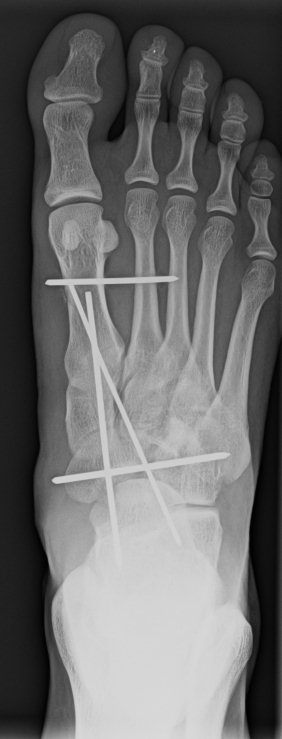

Kriplíci, úrazy, zranění a simulace